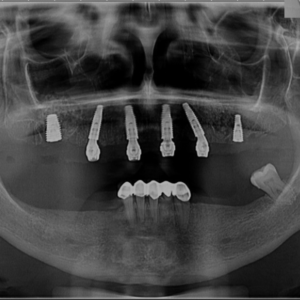

Sub anestezie locală sau sedare, medicul dentist plasează implanturile dentare în osul maxilar sau mandibular. Dacă este necesar, în cadrul aceleiași intervenții se efectuează adiții de os sau extracții dentare. Implanturile de tip All on 4 sau All on 6 sunt poziționate strategic, conform planului stabilit în etapa de evaluare, fiind plasate la unghiuri optime pentru a asigura stabilitatea și integrarea lor. Procedura este nedureroasă și are o durată de aproximativ 1 oră și 30 de minute pentru o arcadă, iar pentru ambele arcade poate dura până la 3 ore.